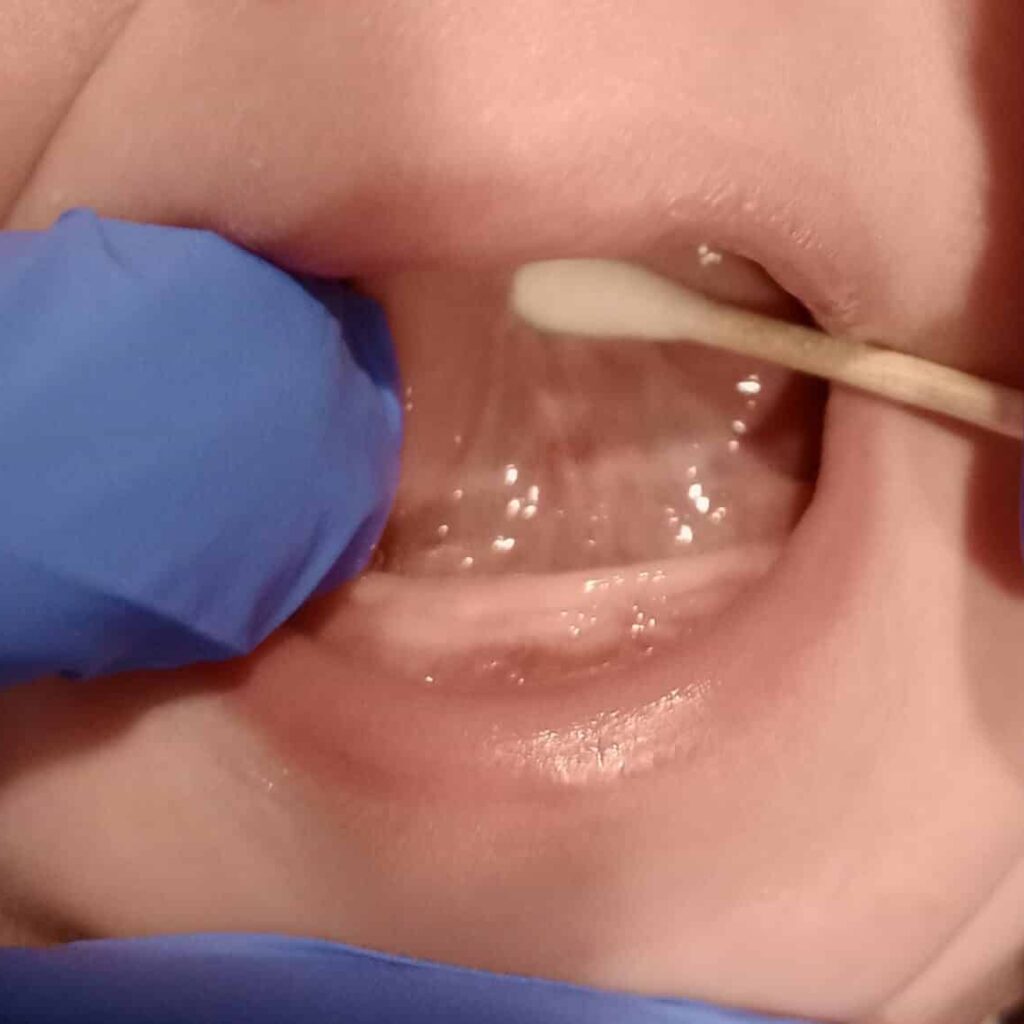

tongue suction post surgery

1 week post surgery follow up